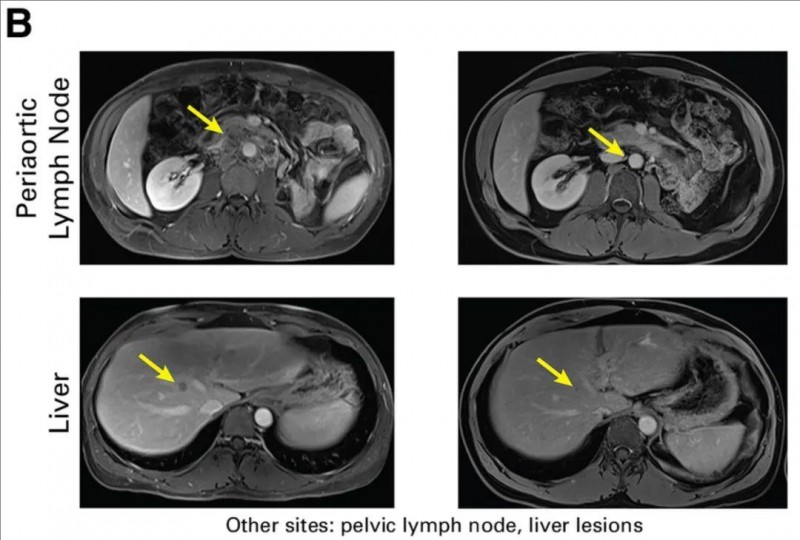

11号尿路上皮癌患者:原发肿瘤累及左输尿管,并伴肝及腹腔淋巴结转移,经手术和化疗后进展,遂接受TCR-T治疗。结果显示:治疗后,主动脉周围淋巴结及肝转移灶持续19个月部分缓解,仅残留少量病灶(详见下图)。

▼转移性尿路上皮癌患者(患者11)在接受TCR-T细胞治疗前(左图)与治疗后18个月(右图)的MRI对比

▲图源“JCO”,版权归原作者所有,如无意中侵犯了知识产权,请联系我们删除